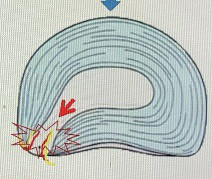

よくあるのは中腰姿勢で重いものをもったりして椎間板が破裂することが多いです。

この椎間板破裂が輪状靭帯をやぶるこれがとにかく痛いです。

矢印のところが椎間板が痛んで炎症し痛みを引き起こしている場所です。

以前は両側性の痛みが多いと言われていましたが、この論文からだと片側も50%は認められたということです。 痛みは動けなくなるくらい痛みや 前かがみをすることで痛いことが多いです。

炎症期はそらしても痛いです。 発生するきっかけは ・何気ない動作 ・ものを取るときに前かがみになった ・中腰での動作 ・重いものを持ち上げる 特に何気ない動作が一番多いです。 治療は炎症由来なのでロキソニン内服とコルセットをして安静にすればすぐに痛みが落ち着きます。

椎間板の痛みなので腰の筋肉をマッサージしても改善はしません。 炎症が落ち着けば痛みはほぼ落ち着き時間と共に改善します。

つまり整体が必要ないという話なんですが、 この椎間板の損傷を繰り返すとだんだん椎間板の水分量が減って椎間板の高さが低くなります。

椎間板の高さが減ることにより神経根の通り道が狭くなり腰部脊柱管狭窄症(足に痛みが出たり、痺れ、力が入らない)の原因になりますので再発を繰り返さないことが大切です。 椎間板は軟骨成分です。半月板と一緒で再生しないのでいかに痛めないかが重要です。